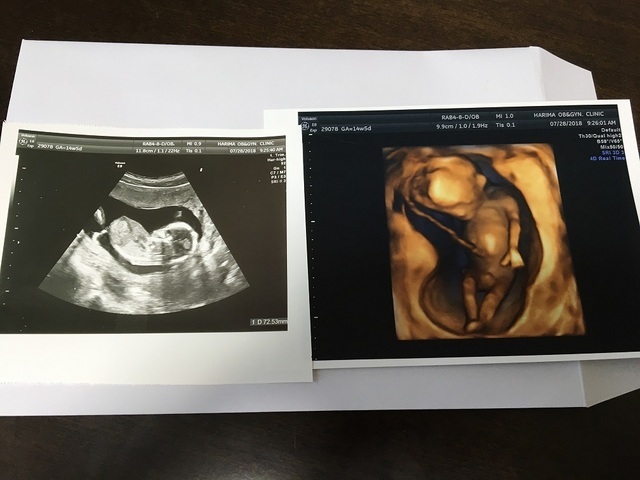

14週0日(14w0d・性別不明)|きなこもっち- さん(32歳)

エコー写真撮影時のエピソード:

病院の都合で、急な転院が決まり転院先で初めてのエコー写真です。新しい病院では、エコーが3Dで見ることができ、立体的な我が子の様子を初めてみて、また動く様子もハッキリと見られてうれしく思ったのを覚えています!

お姉ちゃんになる娘は、まだ分からないようですが、なんとなく感じているのか時々お腹に顔を当てています。まるで、指しゃぶりをしているようなお腹の中の我が子♪早く会いたいです!